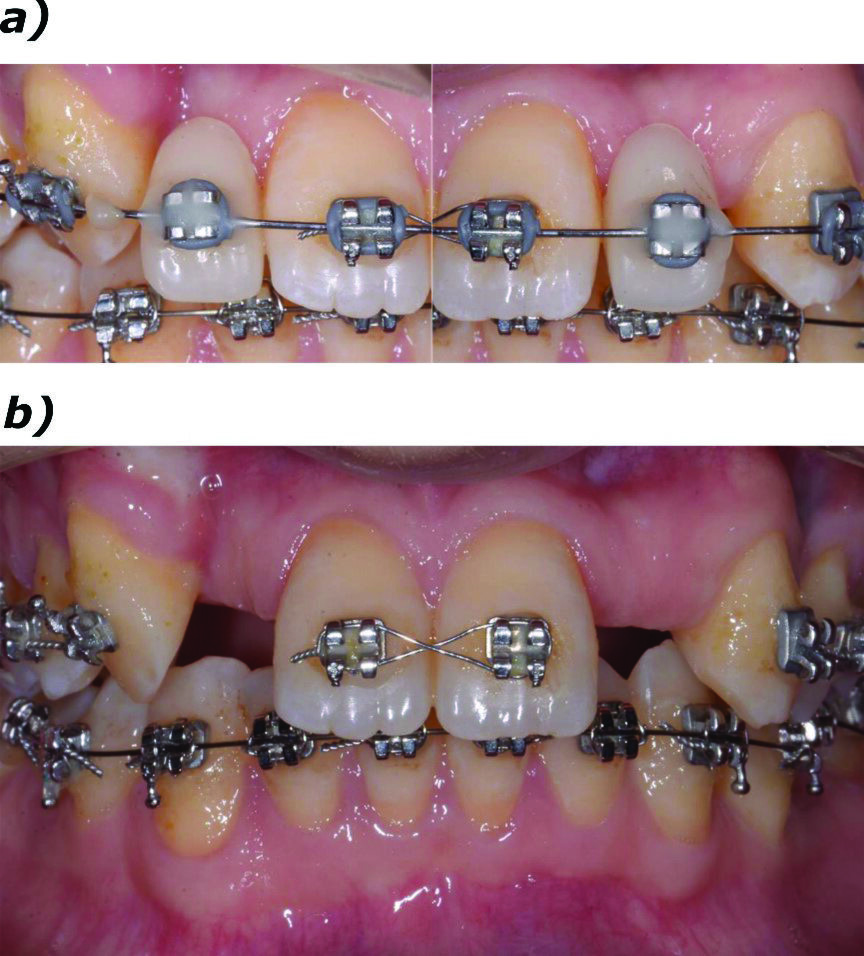

La paziente, donna di 26 anni, presentava agenesia bilaterale degli incisivi laterali superiori. Affermava di voler risolvere la problematica il più velocemente possibile per motivi di natura sia psicologica sia economica, esprimendo il desiderio di ottenere una riabilitazione funzionale ed estetica tramite un intervento finalizzato alla realizzazione di una protesi fissa. È stato quindi prospettato un approccio terapeutico multidisciplinare basato su trattamento ortodontico per migliorare l’allineamento e ottimizzare lo spazio per il posizionamento implantare. Dopo accettazione e firma del consenso, si è proceduto al trattamento ortodontico fisso. In una prima fase, due elementi provvisori a pura funzione estetica sono stati apposti all’apparecchio ortodontico (Fig. 1a). Ottenuto il risultato ortodontico a distanza di 12 mesi (Fig. 1b), si è potuto procedere con l’inserimento di impianti B1ONE (IDI Evolution) a diametro ridotto.

Fig. 1_Presentazione del caso. Il paziente presenta agenesia bilaterale degli incisivi secondari superiori; a) trattamento conservativo con provvisori in resina solidarizzati all’apparecchio ortodontico e a sola funzione estetica; b) trattamento ortodontico per l’ottimizzazione del piano occlusale e dello spazio mesio-distale.